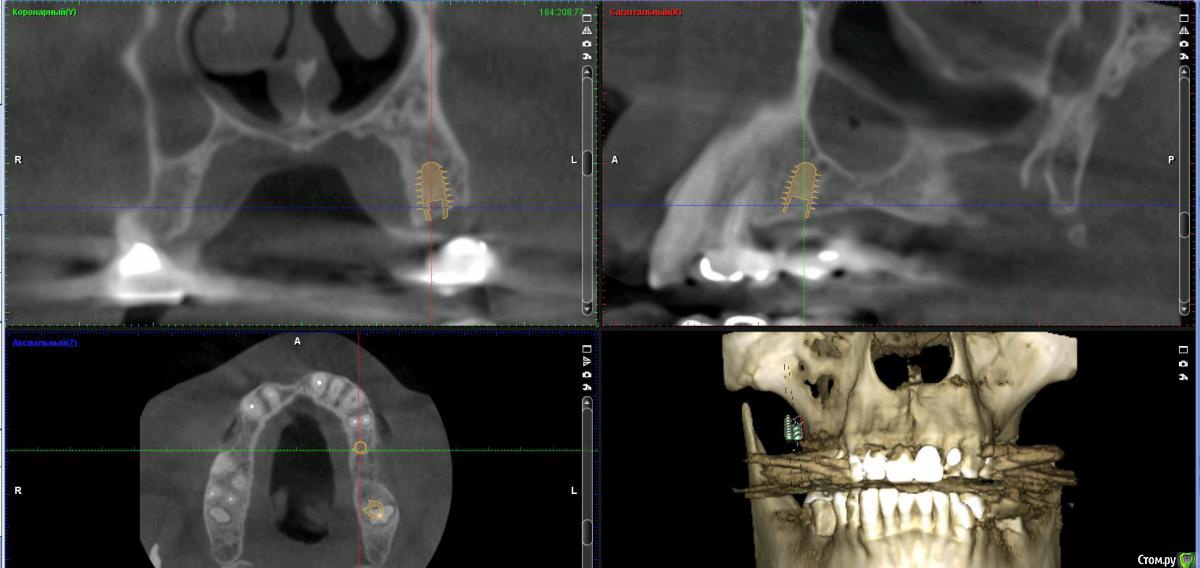

Дмитрий Л. Опубликовано 16 ноября, 2018 Поделиться Опубликовано 16 ноября, 2018 (изменено) Здравствуйте всем)Ситуация такая: старый мост 24-28. 28 симптоматичен, пациент принимает аб и противовосп. Имеется: - 24 перирадикулярные изменения (асимптомно)- 28 перирадикулярные изменения (обострение)- утолщение слизистой гайморовой (асимптомно)- невозможность имплантации в обл 26 (высота кости не позволяет) Пожелания пациента:- удаление 28 - желание сохранить мост - имплантация - нежелание носить съемную конструкцию Как планирую я:- перелечить 24, кальций 2-6 мес.- удалить 28- изготовить съёмник- выждать 4-6 мес. Повторить КТ, оценить гайморовую- имплантация 25, имплантация "где-то в обл 27" - всеми силами избежать синуса Мои грёзы:1. Ставить вблизи 24 - риск. Нужно лечить 24... реэндо... долго... может удалить? 2. Я верю, что причина хр гайморита - 28. Так ли это? Стоит ли ожидать позитивной динамики? 3. На сколько уйдёт кость после удаления 28 за 4-6 мес.? Её и так мало... Станет ли меньше? Графтить 28 не хочу. Там микробы. 4. Объём кости в обл 27-28 требует коротышку. Первыми приходят на ум Штрауман 6 мм (4 мм в кости, станет красиво) или ЭниРидж (бикортакально, скорее всего в пазуху на 1-2 мм). Нюанс в том, что я не работал этими системами... И коротышки не ставил. В общем придётся искать наборы, но это мои проблемы. 5. Итоговая конструкция: мост 25-27. При чём 27 имеет длину 4-6 мм, не слишком ли короткая дистальная опора? Вот спланировал приблизительно так... Надеюсь на отклик. Изменено 16 ноября, 2018 пользователем Дмитрий Л. Ссылка на комментарий

Irouil Опубликовано 16 ноября, 2018 Поделиться Опубликовано 16 ноября, 2018 (изменено) Без синуса это 2.5-2.8? Мне кажется надо синусить и нормально имплантировать, только с носом разобраться предварительно Апдейт: перечитал тс, 2.5-2.7. я бы, перед тем как стучать, сделал КТ соустья. Изменено 16 ноября, 2018 пользователем Irouil 1 Ссылка на комментарий

Bier Опубликовано 16 ноября, 2018 Поделиться Опубликовано 16 ноября, 2018 25-27 совершенно согласен. Я вангую, что и так туда 8мм войдет. Отрочено да. Я люблю отсрочено верхнюю челюсть делать. 1 Ссылка на комментарий

Neilrus Опубликовано 16 ноября, 2018 Поделиться Опубликовано 16 ноября, 2018 У эниридж есть совсем коротыши 5,5х5, для семерки, если не хотите лезть в синус самое то, у него огромная площадь получается за счет особенностей резьбы. Только для него набор специальный с ограничителями должен быть, но дилер может и даст в аренду за имплантат, покупать его не вижу смысла, нужен раз в полгода 1 Ссылка на комментарий